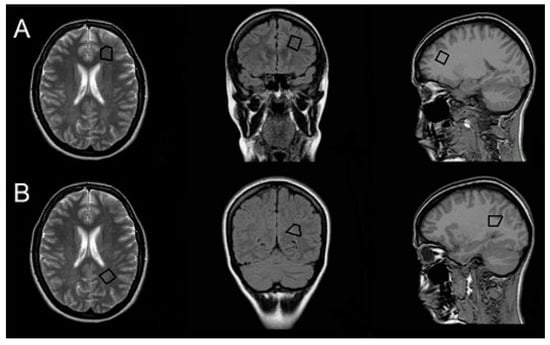

1H-MRS was acquired at the same time as conventional MRI with the same scanner before the gadolinium-based contrast agent was administered. For planning and locating the target voxel, the following scans were acquired: transverse T2 TSE (TR, 4847 ms; TE, 100 ms; ST, 5 mm), axial T1 (TR, 135 ms; TE, 1.79 ms; ST, 5 mm), and coronal FLAIR (TR, 600 ms; TE, 120 ms; inversion time, 2000 ms). Then, a single-voxel 1H-MRS was acquired for the following two volumes of interest (VOIs; 2.7 mL) in NAWM in the left hemisphere: (i) the frontal region anterolaterally to the frontal horn of the lateral ventricle; and (ii) the parietal region superolateral to the trigone of the lateral ventricle (Figure 1). The VOI was defined manually using scans in the transverse, axial, and coronal planes to maximize the area of NAWM sampled while excluding cerebrospinal fluid, gray matter, and demyelinated lesions. In cases where the VOI could not be placed in the left hemisphere because of lesions, the right hemisphere was chosen as there is no evidence for hemispheric differences in the NAWM 1H-MRS measures [,]. A point-resolved spectroscopy sequence with TR of 2000 ms and TE of 31 and 144 ms was used in the 1H-MRS acquisition. Water was suppressed with the chemical shift selective saturation technique (CHESS). Water suppression and shimming were optimized automatically. A medical physicist experienced in 1H-MRS analysis performed postprocessing with SpectroView software (Philips). We semi-quantitatively assessed metabolite concentrations by calculating relative peak area ratios for N-acetyl-aspartate (NAA)/creatine (Cr) and NAA/choline (Cho) for long TE (144 ms) and Cho/Cr, myo-inositol (mI)/Cr, and NAA/mI for short TE (31 ms).

Figure 1.

Volume of interest. Positions of volumes of interest (VOIs) in normal-appearing white matter (NAWM) in frontal (A) and parietal (B) regions.